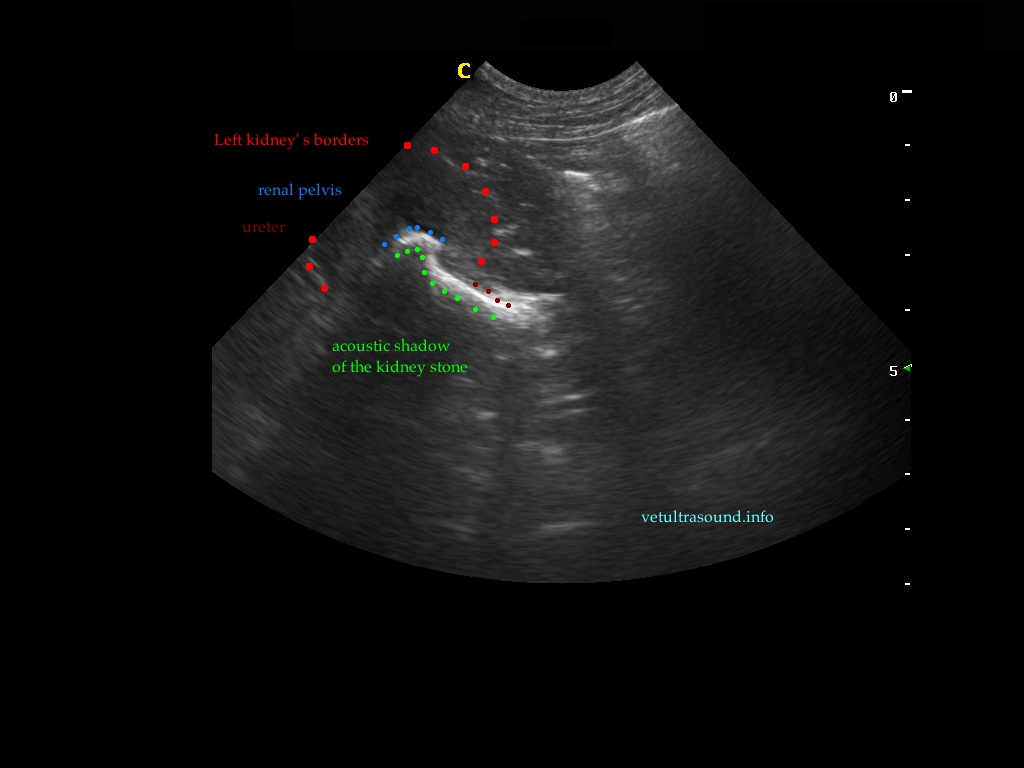

Ευρήματα: Παρουσία λίθου στην πύελο του αριστερού νεφρού ο οποίος καταλάμβανε όλη την κοιλότητά της και εκτεινόταν στο πρώτο τμήμα του ουρητήρα. Ο λίθος προκαλούσε ήπια διάταση του πυελοκαλυκικού συστήματος και του ουρητήρα. Αντίστοιχα στον δεξιό νεφρό βρέθηκε λίθος ο οποίος εντοπιζόταν μόνο στην κοιλότητα της νεφρικής πυέλου. Στην ουροδόχο κύστη βρέθηκε μικρή παρουσία ιζήματος.